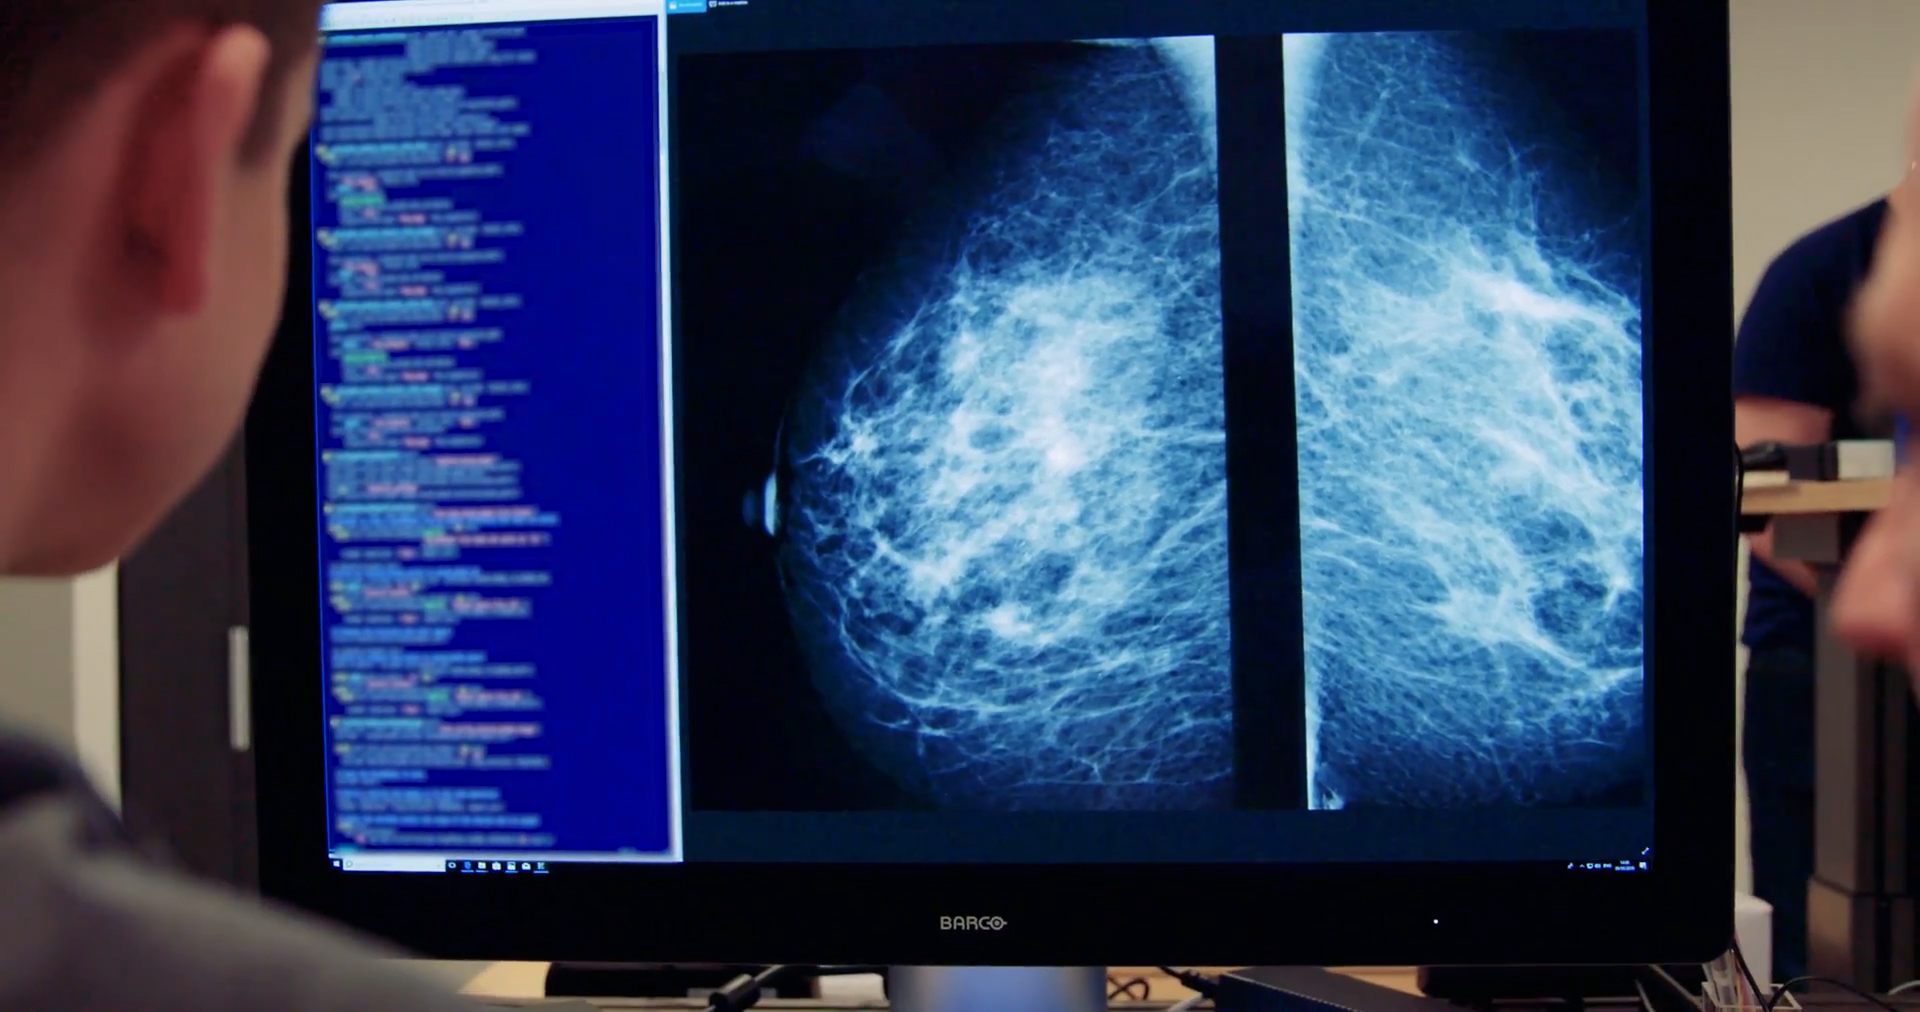

What happened: An AI tool called Mia caught multiple small cancers missed by doctors in a test of 10,000 women’s mammograms performed by Britain’s National Health Service (NHS).

- Mia caught all the scans with cancers that radiologists also found, in addition to 11 that they missed.

- Mia could make breast cancer screening both more effective (by catching cases that would’ve otherwise been missed) and less labour-intensive.

- The NHS, for example, requires two radiologists to review every mammogram — a tool like Mia could someday replace one of those people, effectively doubling productivity.